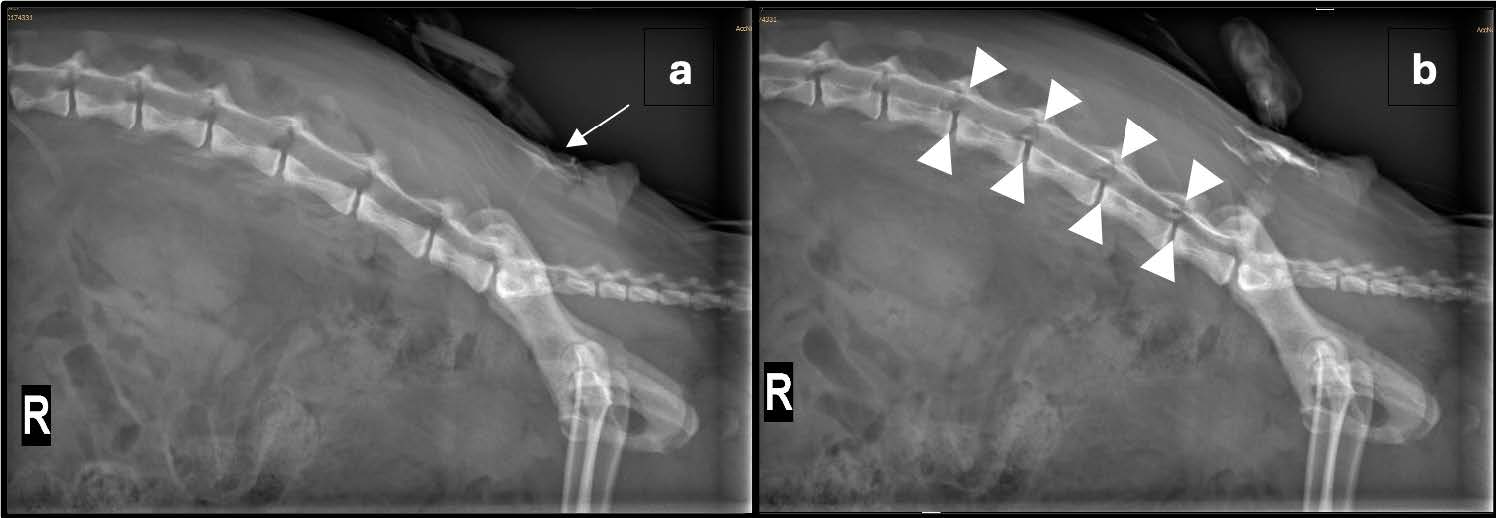

鉴于创伤的严重性,使用Tuohy硬膜外腔针在患者处于胸卧位时放置了一根硬膜外腔导管。随后拍摄了一张侧位X光片,并将导管推进5厘米。通过导管注入稀释的非离子型碘化造影剂(0.5 mL碘海醇稀释于1 mL 0.9% NaCl),最初使用低剂量以观察导管的位置(下图a)。在注入全部造影剂体积后拍摄的重复X光片确认了硬膜外的放置位置和适当的造影剂扩散(下图b)。

↑ (a) 右侧位X光片显示椎柱和骨盆的硬膜外导管(箭头)在注入少量造影剂后的位置。(b) 通过硬膜外导管注入0.5 mL非离子型碘化造影剂后的重复右侧位X光片。硬膜外导管的尖端并未清晰显示;通过比较造影前后的图像,可以看到少量的造影剂到达L3-4神经孔(箭头所围区域)。探查性剖腹术后腹部出现了弥漫性不均匀的浆膜细节缺失和多灶性游离气体。